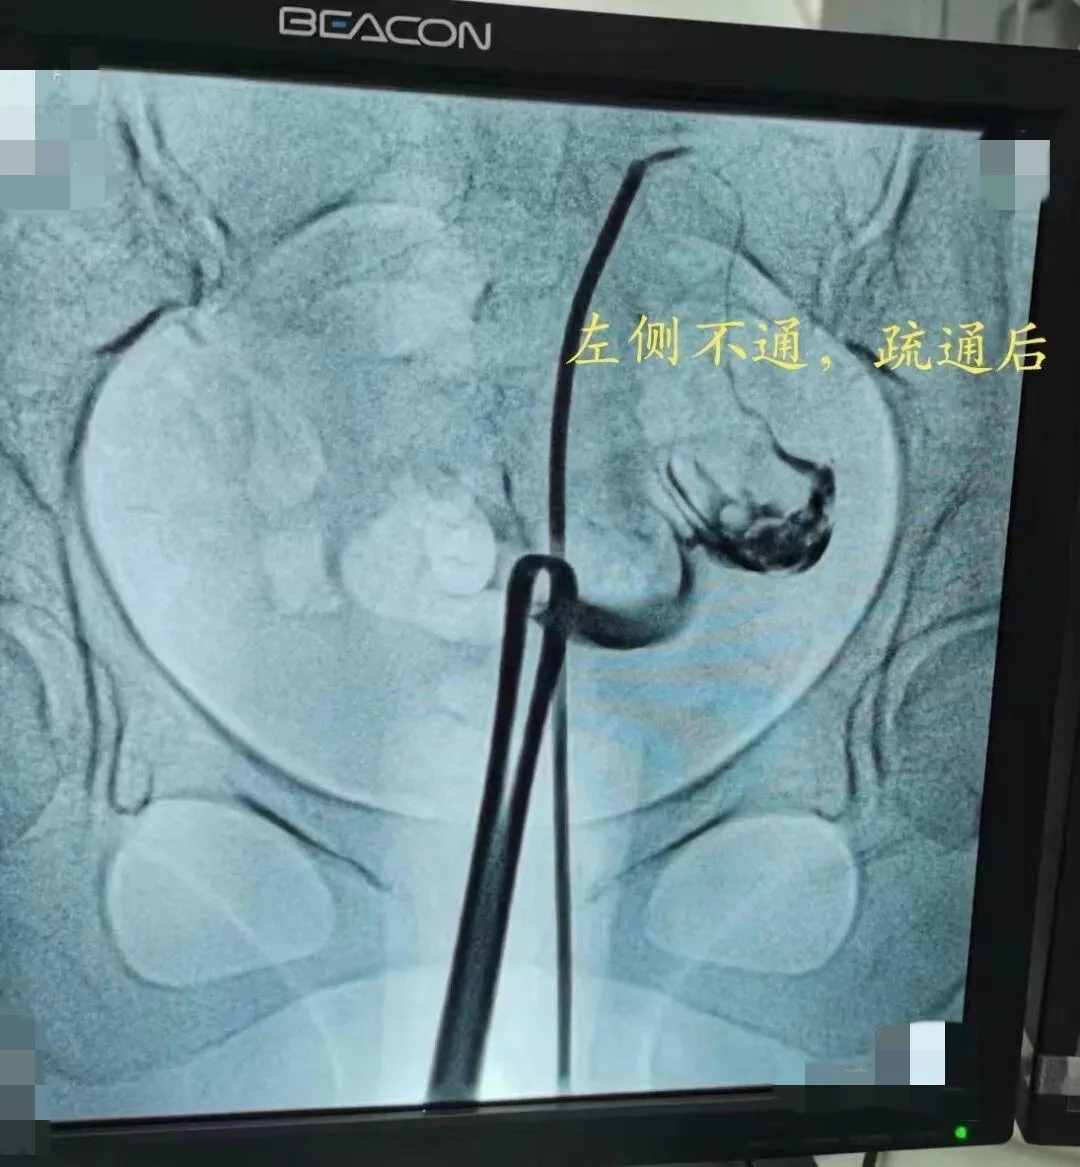

近日,我院收治了一位被不孕症困扰多年的患者,该女士5年来,因为不孕反复就诊多家医院和诊所,中药西药没少喝,却迟迟没有迎来“好孕”。1月前,她慕名来到我院的妇科门诊,在周愦珍主任的建议下,进行了输卵管造影术,结果显示左侧输卵管不通,右侧输卵管上举迂曲。患者得此消息,焦虑不已。周主任团队为其精心制定手术方案,进行了“输卵管导丝介入疏通术”,短短几分钟,为患者解决了困扰多年的问题,夫妻俩开心极了,直言“好孕”到了!

“输卵管导丝介入疏通术”是从美国引进的技术,主要用于治疗输卵管堵塞导致的不孕症。输卵管导丝介入疏通术,采用微创技术,可作为输卵管近段阻塞的首选再通方法,操作简单,不开刀、无痛苦,安全有效,不良反应轻,可达到诊断与治疗的双重目的,已在临床得到推广普及。该技术是集检测、扩容、通液三位一体的高精人工智能辅助生育技术。它通过dsa造影技术精确确定堵塞部位,利用在妇科腹腔镜、宫腔镜两大技术领域的探查与治疗优势,在电视监视和输卵管镜的直视下无创精确介入,将一根导管通过阴道放至子宫输卵管的开口部位,管中有根0.38毫米的铂金导丝,这根导丝比我们的头发丝还要细,经宫颈将导管导丝送入输卵管阻塞部位,然后在电视监视和输卵管镜的直视下,通过局部介入技术将输卵管疏通,并置入预防粘连的药物,对患者进行子宫输卵管疏通手术。